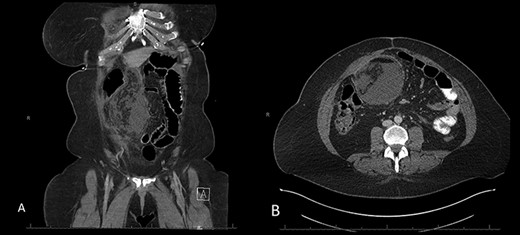

The patient is a 46-year-old female with a pre-operative body-mass index (BMI) of 48 kg/m2 who underwent an uneventful laparoscopic RYGB with a 50-cm biliopancreatic limb and 100-cm alimentary limb and an antecolic, antegastric-stapled gastrojejunostomy using a 21–3.5-mm circular stapler in addition to the repair of a small sliding hiatal hernia. A thick omentum was divided in the midline, starting at the level of the mid-portion of the transverse colon moving distally through the edge of the omentum (Fig. 1). The procedure was uneventful, and the patient was discharged home on postoperative day 1. She had a scheduled follow-up visit at 2 weeks and was progressing as expected. Three weeks postoperatively, she presented to the emergency room complaining of two-day history of severe, diffuse abdominal pain. Initial vital signs were normal and laboratory values were WBC of 6.7 109/L, creatinine 0.76 mg/dl and lactate of 1.2 mmol/L. CT scan was obtained (Fig. 2A and B) that demonstrated 17.7 cm partially encapsulated mixed attenuating area on the right side of her abdomen, suggestive of omental infarction with necrosis. There was no evidence of leak from GJ or JJ anastomoses on CT with oral contrast, which was subsequently confirmed on upper GI with small bowel through. She was admitted for observation. Over the course of the next day, she reported worsening abdominal pain and developed tachycardia to 117 and BP of 89/68 mmHg. Repeat WBC count was 12.7 109/L, creatinine 1.29 mg/dl and lactate of 5.0 mmol/L.

A and B: Abdominal and pelvic CT scan obtained at POD # 21 readmission for abdominal pain showing a 17.7-cm mixed attenuating lesion extending anterior to the transverse colon into the upper-pelvis-associated stranding and fluid level suggestive of omental infarction and liquefied necrosis.